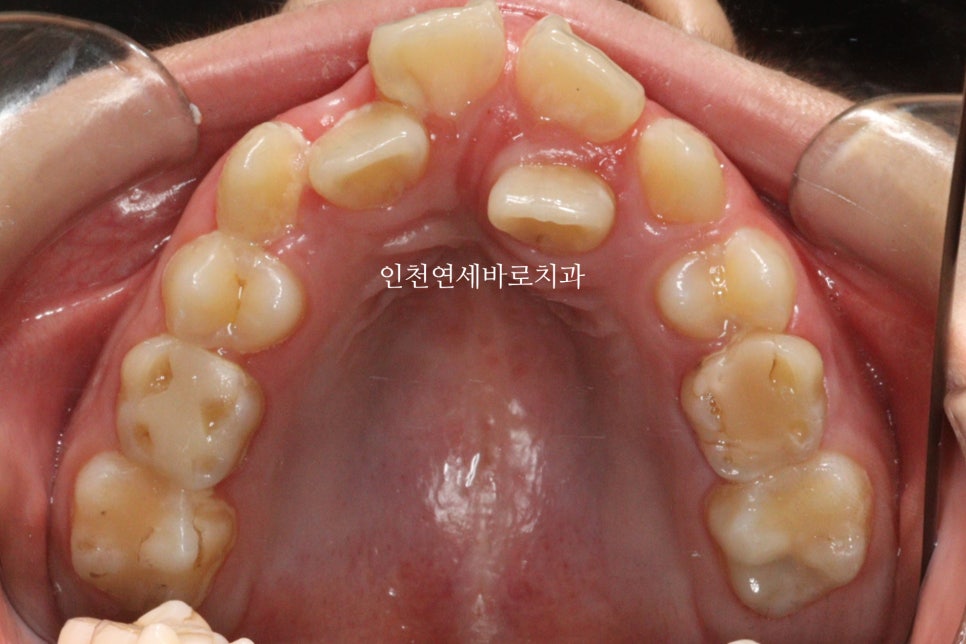

처음 시작하고 약 7개월 정도가 지났을때의 모습입니다. 아직은 삐뚠 치열이 남아있지만, 어느정도 정리가 되어가고 있네요